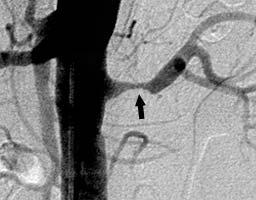

| Стеноз левой почечной артерии атеросклеротической бляшкой (черная стрелка) |